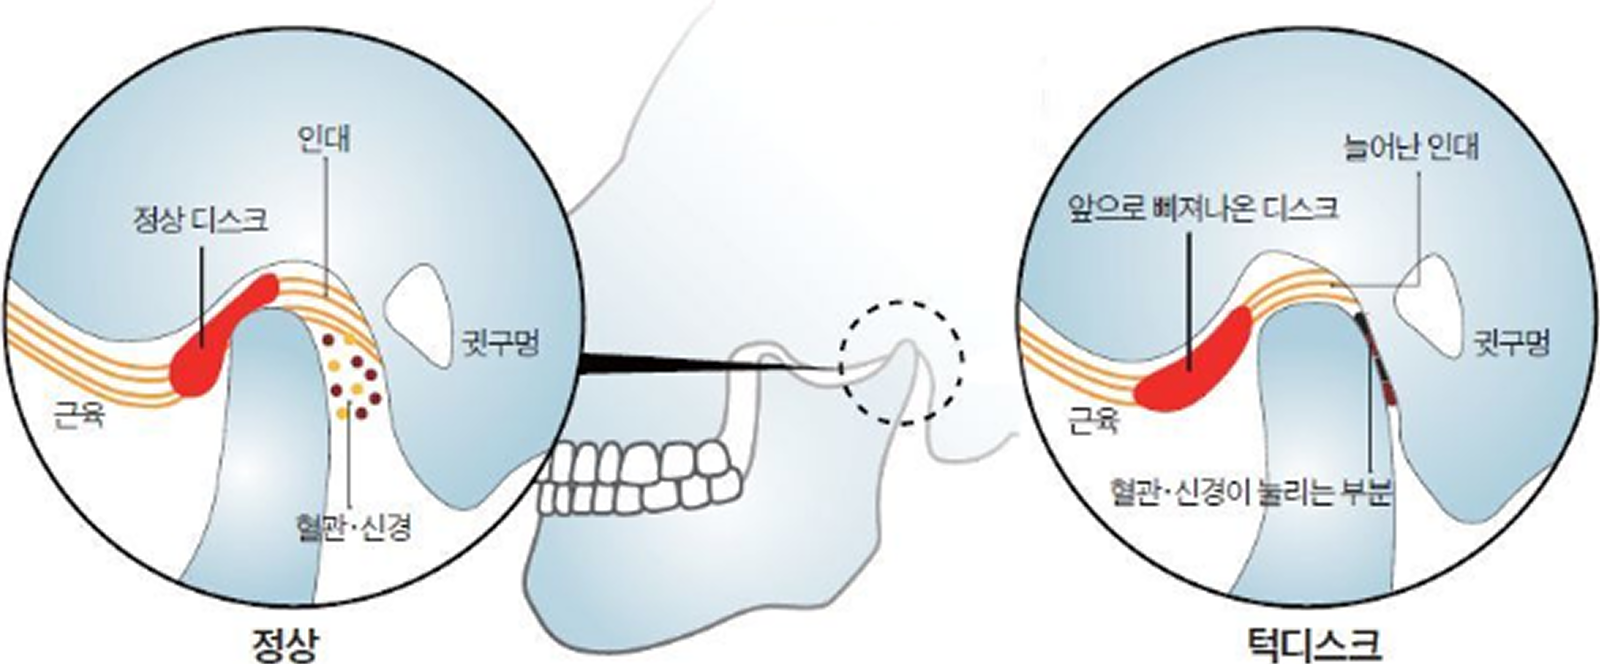

턱관절치료

턱관절치료

턱관절치료

턱뼈와 두개골을 연결하는 관절의 통증 및 기능 장애 해결을 위하여 구강학적 접근으로 물리적, 약물적 치료를 병행합니다.